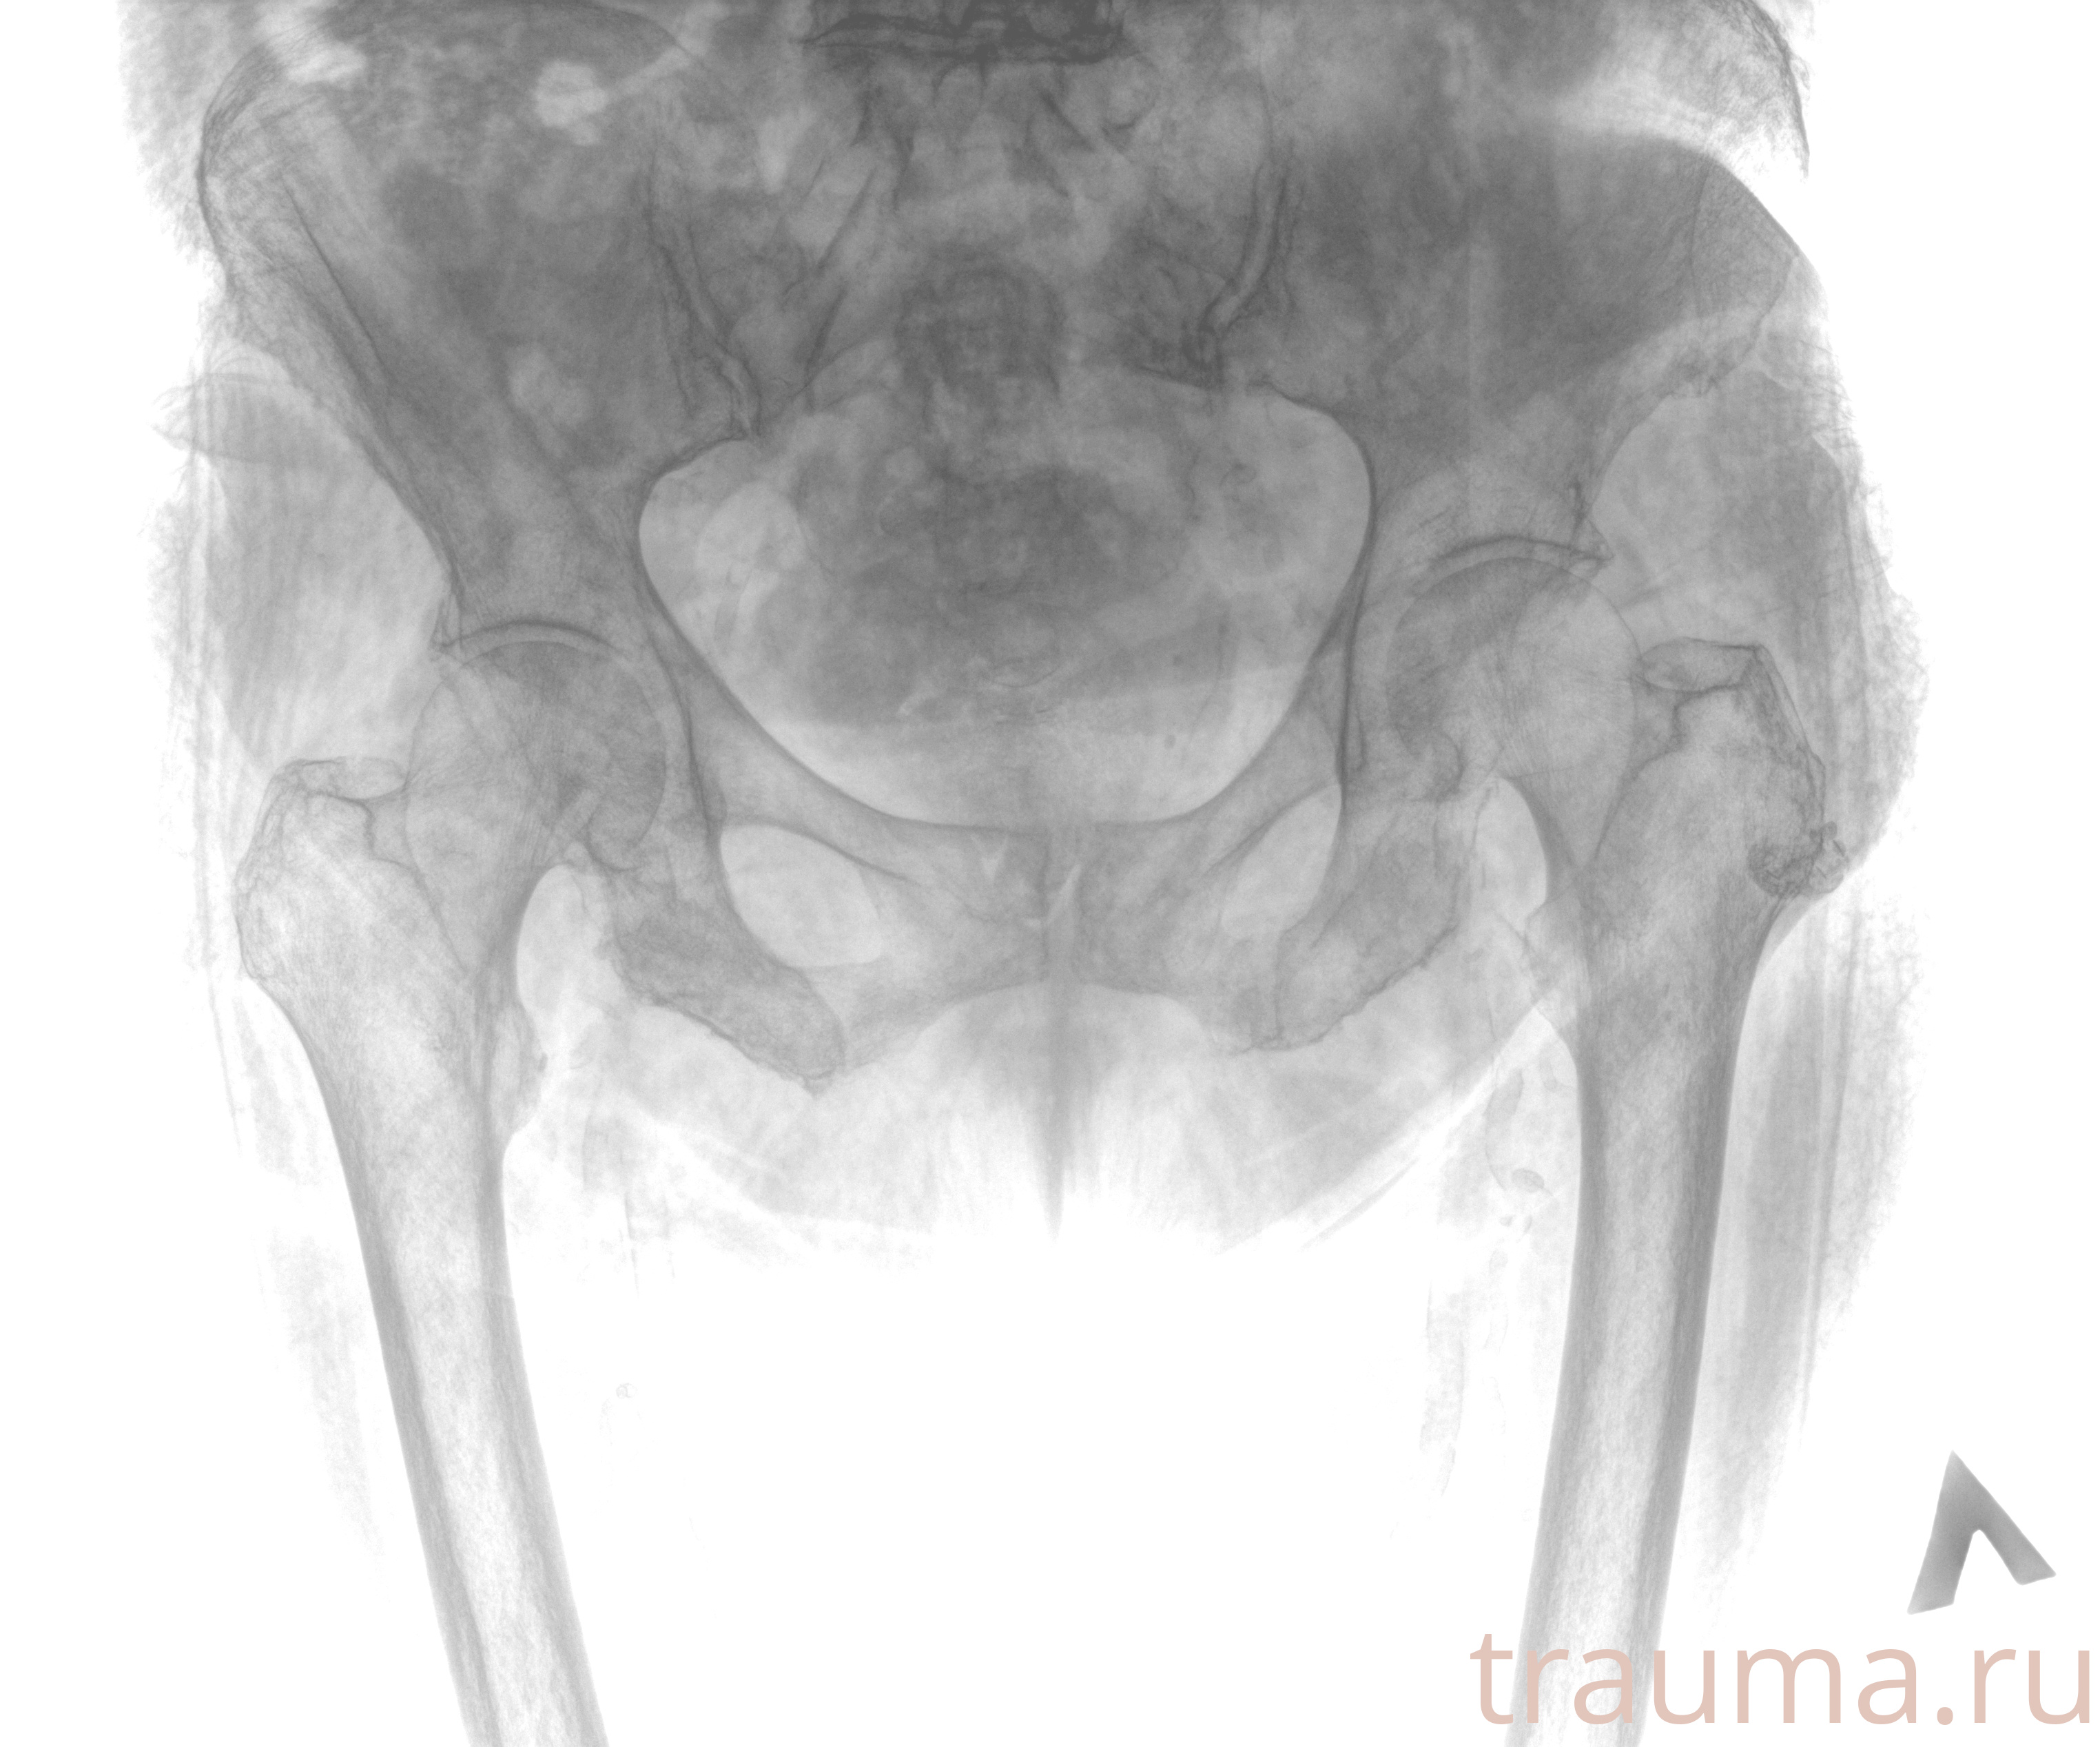

Рентгенограммы

Рентген на дому: по вашему адресу приезжает врач-рентгенолог, травматолог-ортопед с мобильным рентгеновским аппаратом, проводит диагностику травмы или заболевания, делает необходимые рентгенограммы, дает рекомендации по дальнейшему лечению. Получить качественные снимки в домашних условиях возможно благодаря уникальной методике, разработанной МосРентген Центром для института  Склифосовского

при переломе шейки бедра и пневмонии от компании МосРентген Центр - партнера Института имени Склифосовского